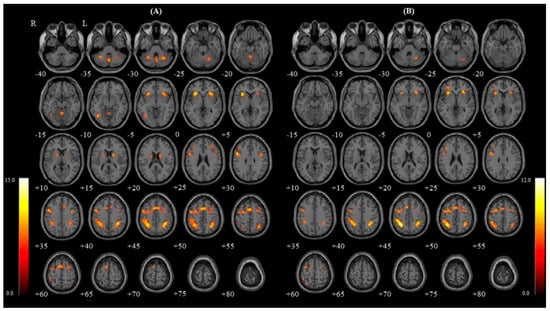

| Nasal | R | Inferior parietal gyrus | 801 | 15.18 | 7.15 | 36 | −44 | 44 |

| Caudate nucleus | 133 | 11.33 | 7.15 | 16 | 2 | 18 | ||

| Insula | 291 | 11.26 | 6.34 | 30 | 22 | 0 | ||

| Cerebellum | 229 | 10.44 | 6.13 | 28 | −58 | −28 | ||

| Precentral gyrus | 184 | 10.17 | 6.05 | 38 | 0 | 34 | ||

| Middle frontal gyrus | 265 | 8.66 | 5.59 | 32 | 6 | 58 | ||

| M | Vermis | 413 | 9.89 | 5.97 | 0 | −66 | −34 | |

| L | Insula | 338 | 14.49 | 7.03 | −30 | 20 | 4 | |

| Precentral gyrus | 888 | 12.68 | 6.67 | −50 | 8 | 32 | ||

| Inferior parietal gyrus | 1295 | 12.68 | 6.67 | −30 | −48 | 44 | ||

| Inferior occipital gyrus | 177 | 11.42 | 6.38 | −40 | −62 | −8 | ||

| Supplementary motor area | 865 | 11.33 | 6.36 | 0 | 10 | 54 | ||

| Cerebellum | 127 | 10.39 | 6.11 | −30 | −54 | −30 | ||

| Middle frontal gyrus | 59 | 8.53 | 5.55 | −44 | 30 | 32 | ||

| Putamen | 153 | 8.24 | 5.45 | −20 | 4 | 12 | ||

| Oral | R | Inferior parietal gyrus | 568 | 11.48 | 6.39 | 36 | −46 | 46 |

| Putamen | 191 | 10.85 | 6.23 | 26 | 26 | 2 | ||

| Cerebellum | 102 | 8.81 | 5.64 | 26 | −62 | −28 | ||

| Superior frontal gyrus | 181 | 8.37 | 5.49 | 26 | 4 | 58 | ||

| L | Inferior parietal gyrus | 1201 | 13.89 | 6.92 | −32 | −48 | 46 | |

| Insula | 191 | 10.95 | 6.26 | −30 | 22 | 2 | ||

| Middle frontal gyrus | 73 | 10.61 | 6.17 | −30 | 44 | 2 | ||

| Supplementary motor area | 284 | 9.34 | 5.81 | 0 | 12 | 52 | ||

| Precentral gyrus | 655 | 9.15 | 5.75 | −46 | 4 | 30 | ||

| Inferior frontal gyrus, triangular part | 59 | 8.72 | 5.61 | −36 | 26 | 26 | ||